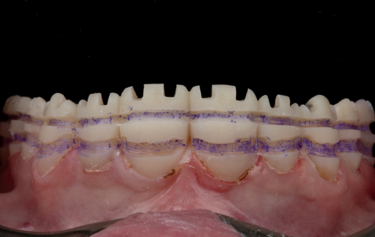

Figure 24: Frontal retracted view – after

Figure 26: Direct comparison of the digital design versus the final restorations

On receiving the scans of the final tooth preparations, the laboratory was able to overlay the planned final restorations which the milled temporaries had been based upon. The small modifications to the occlusion which was completed at the earlier temporary stage could be adapted into the digital design, and then the individual restorations adapted to the refined finishing margins of the final tooth preparations (Fig. 14). The final restorations were then milled in IPS e.max ZirCAD Prime Esthetic in the lighter BL4 shade using the PrograMill PM7 milling unit. New working models were 3D-printed of the preparations, and a second set of oversized models were made to compensate for the increased size of the pre-sintered Zirconia (Fig.15). The larger model was scaled up to match the shrinkage factor of the zirconia to allow the restorations to be checked on the oversized model. This additional check stage allows for assessment of marginal fit and contact areas, in addition to checking the passivity of fit and the occlusion, ahead of sintering.

Some subtle surface shade modifications were then completed using a pre-sintering infiltration technique and IPS e.max zirconia colouring liquids (Fig. 16). Some B1 dentine shade was used in the cervical third to increase the chroma, and some blue and grey was used towards the incisal third to increase the appearance of translucency. A little orange shade was also used in the occlusal area of the posterior teeth. The restorations were dried in line with manufacturer recommendations, and they were then sintered in the Ivoclar S1 1600 furnace. After sintering the crowns were checked on the regular-sized working model, and because all these checks had already been made pre-sintering then there were no adjustments necessary. Additional surface texture was added and then the restorations were polished using rubber polishers. Some final characterisation was added using IPS Ivocolor and glazed with IPS Glaze Fluorescence. The final restorations have the perfect balance of individual character and depth of colour to mask the underlying tooth preparation, as well as the graduation of translucency to replicate that of natural teeth (Fig. 17).

The patient returned after two weeks, and the final restorations were once again assessed. All margins, occlusion and excursions were re-checked and there were no further adjustments necessary (Fig. 24 & 25). Note the beautiful tooth morphology and the detailed surface texture that is achievable with modern digitally designed tooth libraries and state-of-the-art milling machines. The transfer of digital design to final restoration is an exact replication and this can be seen on the comparison of digital overlay against the final zirconia restorations in Figure 26

By approaching multiple restorations in the same methodical and planned approach every time, the SmileFast protocol, integrated with a digital ceramic workflow, guarantees predictable and consistently excellent aesthetic results. Figure 6 and 26 show the restored upper arch with composite (Fig. 6) and ceramics (Fig. 26) in direct comparison to the planned digital design; the accuracy of transfer is very precise, with the natural texture and the detailed morphology being replicated exactly.